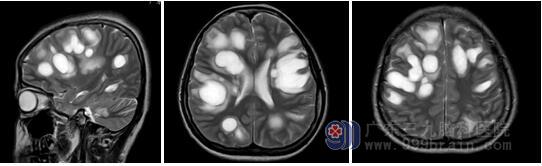

复查头颅核磁时发现,她颅内的病灶更多了,就像是成片的“肥皂泡”。

科室主任王展航教授看病人时,认为患者脑内多发病灶不能完全由外伤解释,进一步追问小美的家人,得知她外伤后接种过破伤风疫苗。这一重要的线索提示小美可能在颅脑损伤的基础上并发急性脱髓鞘脑病。通过进一步追查中枢神经系统脱髓鞘相关抗体,发现血清MOG抗体1:32阳性。最终将致病原因锁定为“MOG抗体介导的特发性炎性脱髓鞘疾病”。

王展航主任分析:髓鞘少突胶质细胞糖蛋白(myelin oligodendrocyte glycoprotein,MOG)抗 体相关的特发性炎性脱髓鞘疾病 (idiopathic inflammatory demyelinating disease,IIDDs),有学者称之为MOG抗体介导的IIDDs(简称为“MOG抗体病”)。50%的患者头颅磁共振平扫可见T2WI上高信号的脱髓鞘病灶,成斑片状弥漫分布,边缘不清,部分病灶有中心强化。大脑半球处病灶可表现为大片状,类似急性播散性脑脊髓炎样改变,部分患者发病前一月内存在疫苗接种史,特异性抗体(MOG抗体)检查对疾病诊断意义重大。MOG抗体病大部分患者急性期治疗后预后较好,对其早期识别及诊治能让患者受益更多。